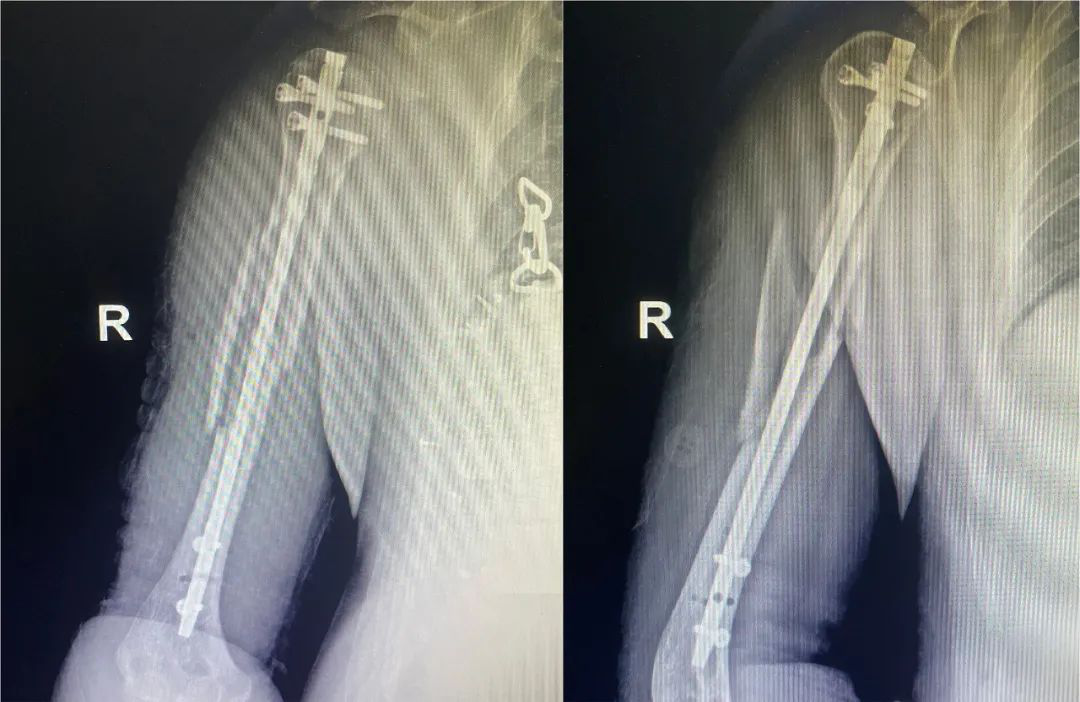

髓内钉固定